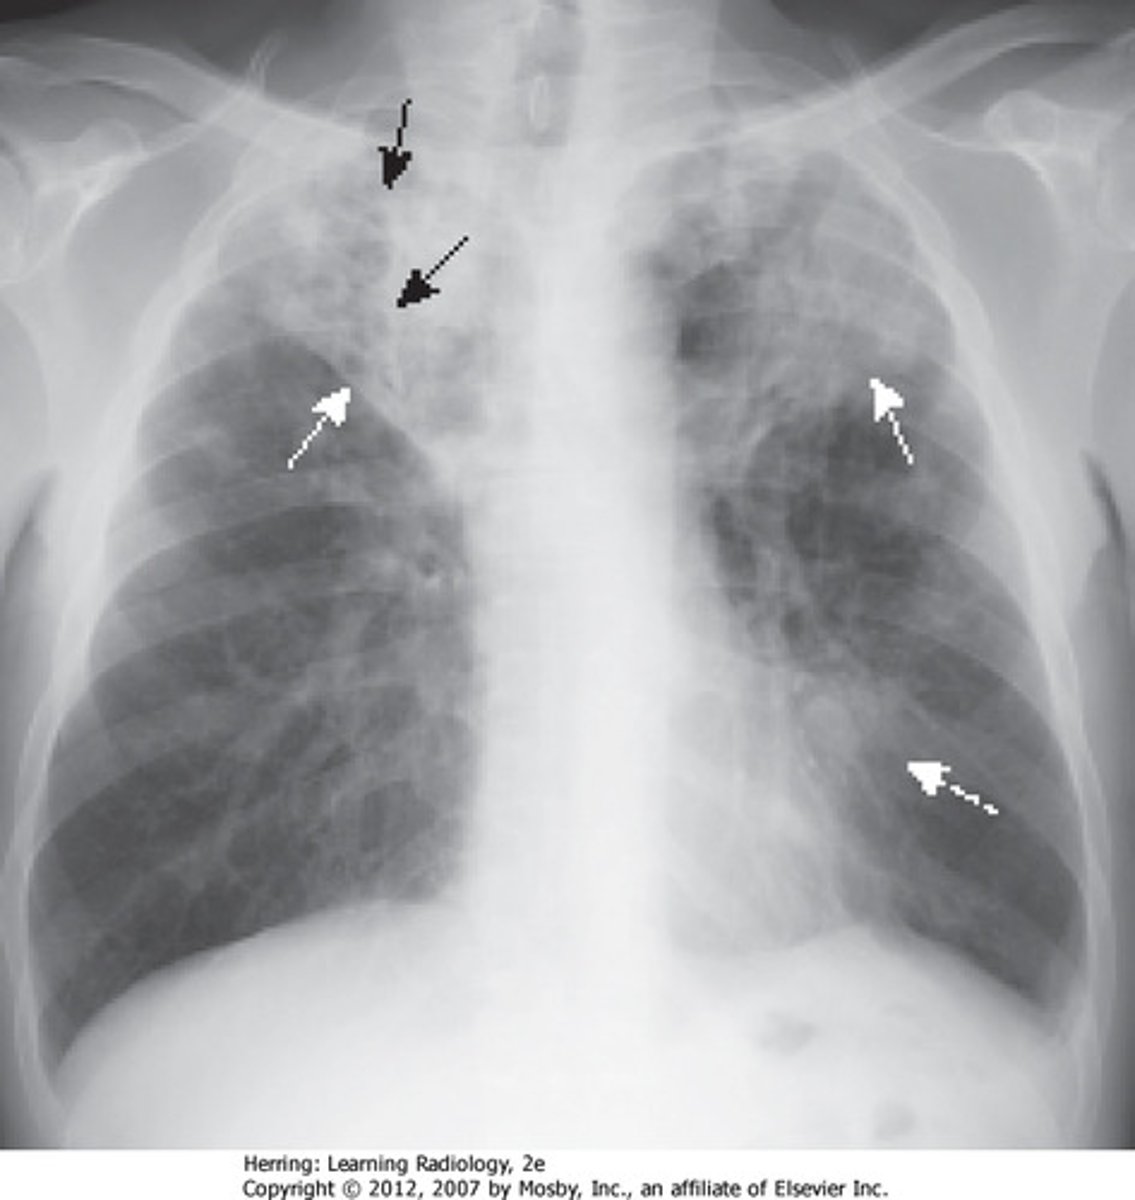

What is seen of CXR with TB?

- unilateral apical infiltrates

- caseating granulomas

- cavitations

- Ghon complexes

- pleural effusion

What is seen on CXR with sarcoidosis?

non-caseating granulomas in multiple organs

What is seen on CXR with sarcoidosis, and what is stage I/ IV?

- I: hilar lymphadenopathy

- IV: overt pulmonary fibrosis